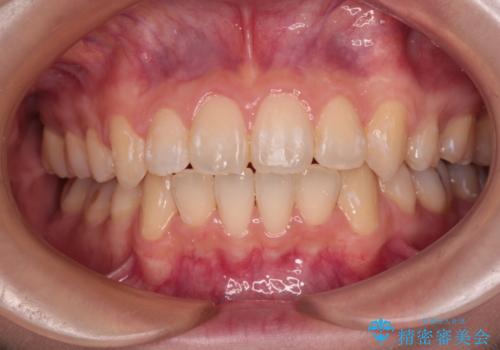

オープンバイトでかみにくい インビザラインによる矯正治療

- 前歯の上下スペースによる食べにくさを気にして来院された患者様です。

インビザラインにより上下の前歯の隙間を閉じていくこととしました。

上下の奥歯を圧下させるようにすることで、前歯を接触させるように計画しました。

上下の隙間に舌が入り込むことがオープンバイトの原因であったため、舌の筋肉のトレーニングも並行して行い、後戻りの抑制を図りました。